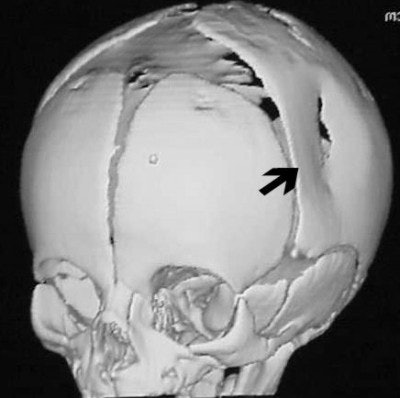

How about CT imaging for an in vitro trauma? Figure CT 5 is an axial image of a newborn child; there were no problems during the caesarian delivery. Two physicians and three nurses were present and the child was noted to have an indentation to the temporal region of the skull. Plain films were positive for a depressed skull fracture (Figure CT 6).

Three-dimensional reconstructed images in surface-shaded volume rendering show an obvious breech of the skull in the affected area (figures CT 7 and CT 8). Detectives matched the defect to a pair of the father’s cowboy boots. He was charged and convicted of beating his wife during the pregnancy.